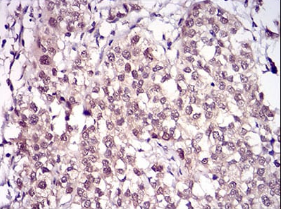

IHC    1/100 - 1/500